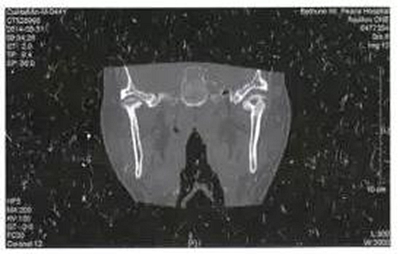

病例3,男,52歲。2月前發(fā)現(xiàn)右側(cè)上頜后牙疼痛,局部腫脹,應用廣譜抗生素后有所減輕,但不能完全恢復。入院10天前右側(cè)面部、顳部腫痛加重,并張口受限明顯?;颊哂刑悄虿∈非抑委煵灰?guī)范。檢查右側(cè)顳部腫脹明顯,張口度10 mm,右側(cè)上頜第三磨牙深齲。CT示右側(cè)翼頜間隙及顳間隙腫脹,右側(cè)緣突骨質(zhì)破壞,在其前方形成液化區(qū)(圖3)。以間隙感染收入院后全麻下手術(shù),口外顳部和口內(nèi)右側(cè)上頜前庭溝聯(lián)合入路,暴露病變的喙突,咬骨鉗去除破壞的喙突,口內(nèi)外貫通引流。繼續(xù)抗感染治療。術(shù)后3周復查基本恢復正常,門診拔除右側(cè)上頜第三磨牙。

圖3右側(cè)喙突骨髓炎